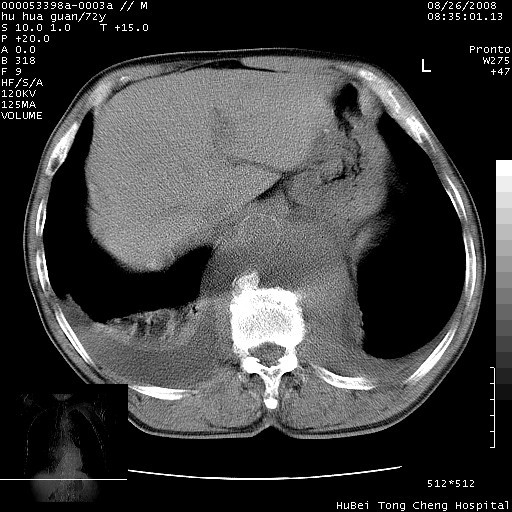

降主动脉前移位,后纵隔占位

后纵隔占位,降主动脉前移位;双侧胸腔积液;应排外食管病变侵犯血管可能;

可以明确的说。肯定不是主动脉夹层破裂出血!考虑为淋巴瘤或间叶组织来源的恶性肿瘤可能性大。右肺小结节建议薄层观察,如能发现恶性征象,那椎前改变就考虑为转移所致。至于双侧少量胸水乃静脉血回流受阻所致。

建议排除结核引起的冷脓肿。